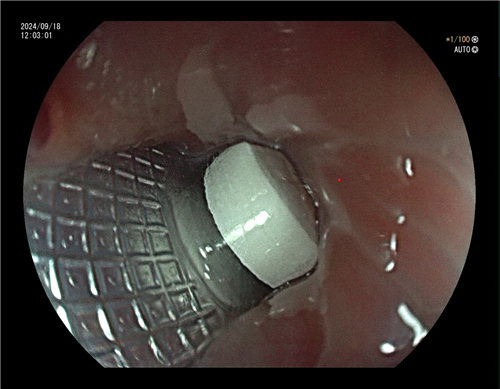

根据老人的症状,张娟医生考虑吞进去的铝箔包装可能卡在了食管里,检查结果证实,老人食管的上段确实有一个直径约1.6厘米长的异物。张娟介绍,正常食管的生理狭窄处直径也仅仅只是1.5厘米左右,长时间的嵌顿会对食管造成极大的损伤,甚至有穿孔、消化道大出血等风险。

消化内科团队考虑目前异物崁顿于食管内无明显穿孔表现,虽然老人身体状况不佳,狭窄的管腔探查非常困难,但有把握将老人的异物取出。在与家属充分沟通后,消化内科团队凭借着精湛的技术和丰富的临床经验,冷静操作,最终有惊无险地将异物取出。